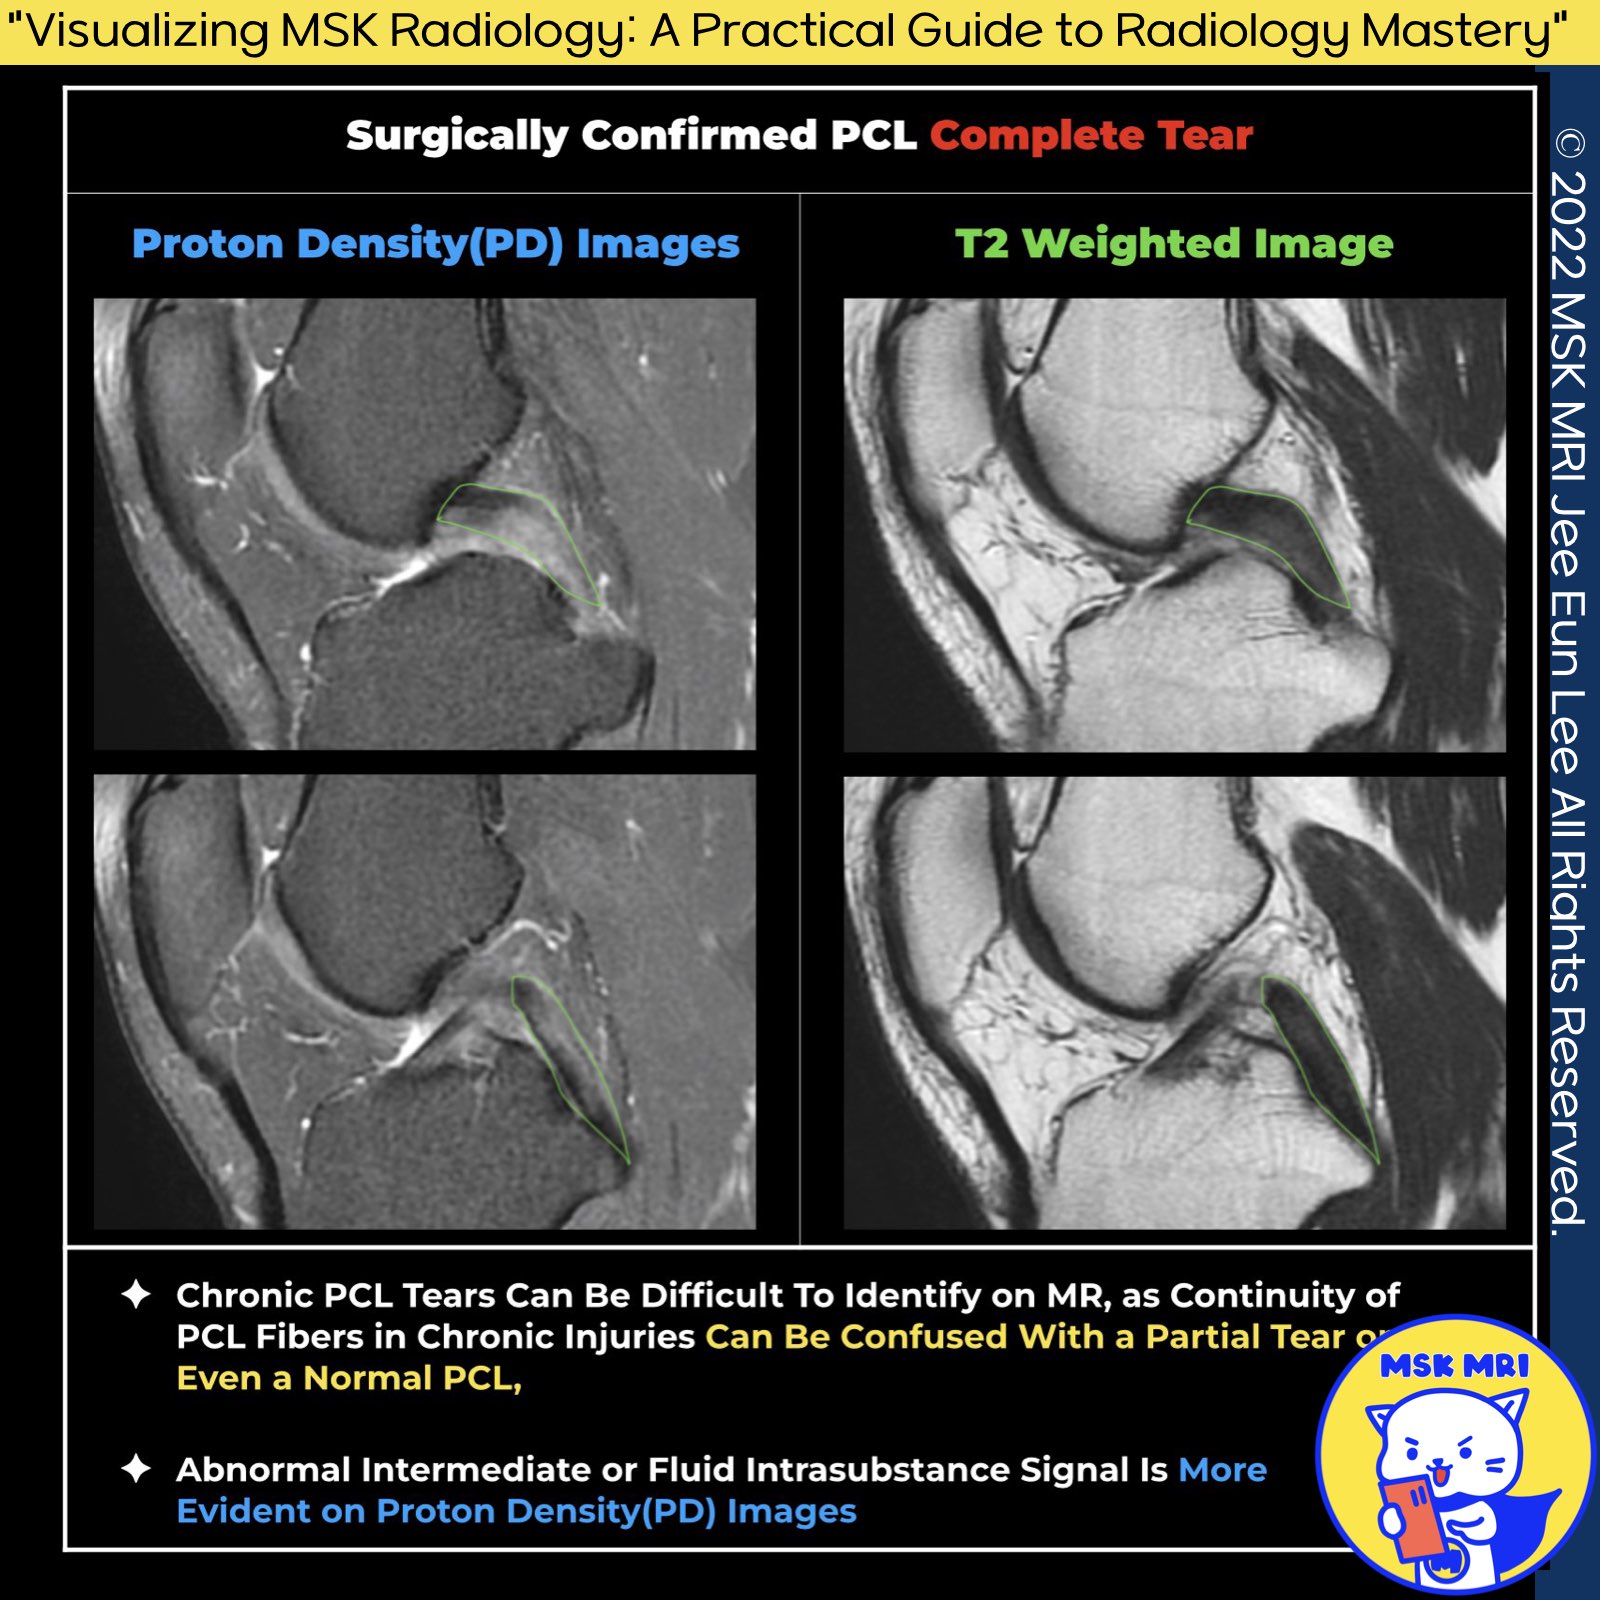

📌 Diagnosing Chronic PCL Tears

1️⃣ : Understanding PCL Appearance on MRI

- Chronic tears of the Posterior Cruciate Ligament (PCL) often present subtle signs that can be challenging to detect on MRI.

- Studies indicate that nearly 28% of chronic PCL injuries might appear almost normal, while another 44% may demonstrate continuity but with noticeable residual morphologic deformities.

2️⃣: The Role of Proton Density Imaging

- Proton density imaging, particularly with fat suppression, is crucial for highlighting subtle pathological changes within the PCL. T

- his technique often reveals increased intraligamentous signal intensity that might not be evident on T2-weighted images.

- For instance, in a case where the PCL diameter and contour appeared normal on T2WI, the proton density sequence unveiled significant abnormalities leading to a correct diagnosis of